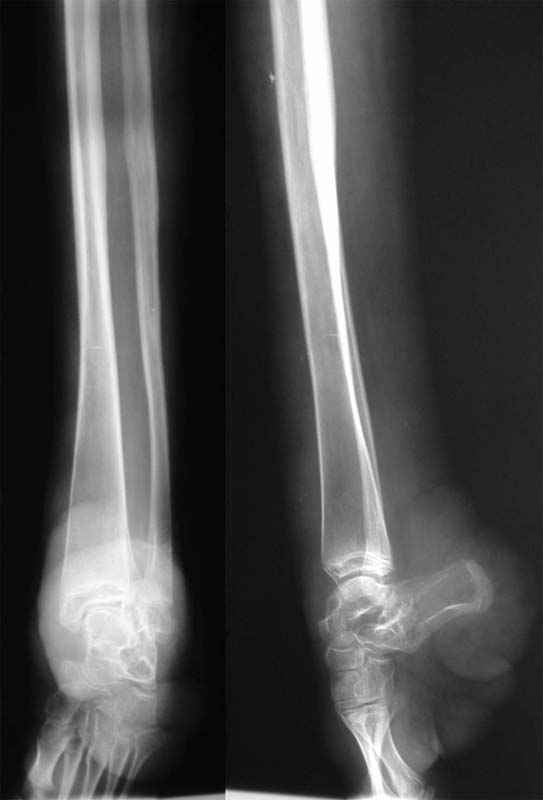

От I беременности, протекавшей с анемией, ОРВИ, угрозой прерывания, I преждевременных патологических родов, девочка 1100 гр., дл. 36 см, Апгар 3/5 б. Отмечается гипоксическое поражение ЦНС, с-м возбудимости, гемангиоматоз, недоношенность III ст. Инвалид детства, на Д-учете.Диагноз: Синдром Клиппеля-Тренона-Вебера, врожденная аномалия левой нижней конечности, деформация левой стопы, ЗТРР в легкой степени, дислалия, лимфоаденоматоз. В 2000 г. - нейро-атритический диатез, ацетонемическое состояние, задержка развития пренатального детерминирования, гипотрофия III ст.Цитогенетическое обследование 09.2008.Объект исследовани: культура лимфоцитов периферической крови, метафазные пластинки хромосом, G-окрашивание.Кариотип 46,ХХЗаключение: хромосомной патологии не выявлено.Носит ортопедическую обувь.Левая нижняя конечность - выраженное ангиоматозное поражение, гигантизм, опережает здоровую конечность на 8 см в длину, постоянный ускоренный рост, контрактуры крупных суставов, стойкая эквинусная установка стопы, не опорна.Рассматривались предложения:1. Ампутация с дальнейшим протезированием.2. Удлинение здоровой конечности.3. Хирургическое устранение эквинуса с последующим удлинением здоровой конечности.Ваше мнение, идеи, комментарии? Выполнение 3 варианта в условиях ангиоматозного поражения? Иные методы, подходы?Заранее благодарю!

По представленным фото и рентгенограммам диагноз: Синдром Клиппеля-Треноне-Вебера (КТВ) вызывет сомнения. Для синдрома КТВ очень характерно наличие варикозно расширеных вен, каппилярных гемангиом на туловище и конечностях, гигантизм конечности при отстуствии грубых деформаций суставов, характерный "крупнозернистый" вид кости на рентгенограммах, отстутвие призанков поражения ЦНС и эндокринных нарушений. Соответвенно и ортопедический этап у этих больных проще: достаточно удлиннить здоровую конечность (фото в приложении).

Имея опыт ортопедического лечения больных с синдромом КТВ, я не имею опыта лечения больных, с такими аномалиями, которые представлены Вами. Чисто теоретически, могу предположить, что лечение надо разбить на несколько этапов: 1 - совместно с пластическими хирургами удалить опухолеподобные массы на стопе, сделав ее приглдной к одеванию обуви, выполнить закрытую корекцию деформации стопы и метатарзальный, а возможно,и большеберцовый эпифизеодез. Меняя выстоту ортопедической обуви на здоровой ноге по мере ее роста обеспечить больной максимальную опороспособность больной ноги. По окончанию периода второго ростового спурта при удовлетворительной опороспособности больной ноги выполнить 2 этап - выполнить эквализацию конечностей (удлиннить здоровую?).

При неудовлетворительных резкльтатах первого этапа - возможно думать и об ампутации. Из послеоперацинных осложнений данной патологии при любом типе операции (даже ампутациях)R.M. Letts (1977) отмечал: профузное кровотчение в раннем п/о периоде, выраженный и длительно сохрянющийся отек, замедленное заживление ран.